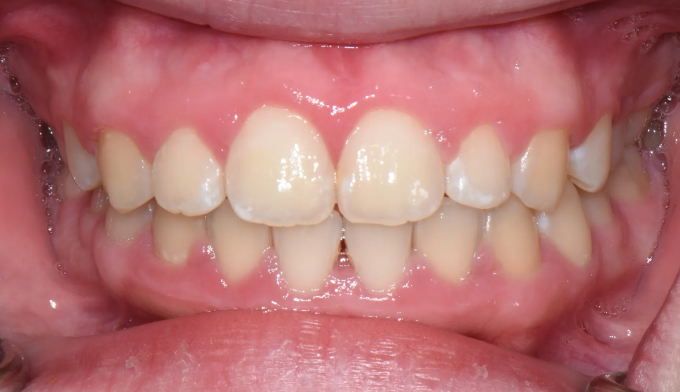

After

발치없이 윗니를 전체적으로 후방이동시켜서 돌출입을 해소하였고, 가지런하지 못한 치열을 모두 배열하였습니다.